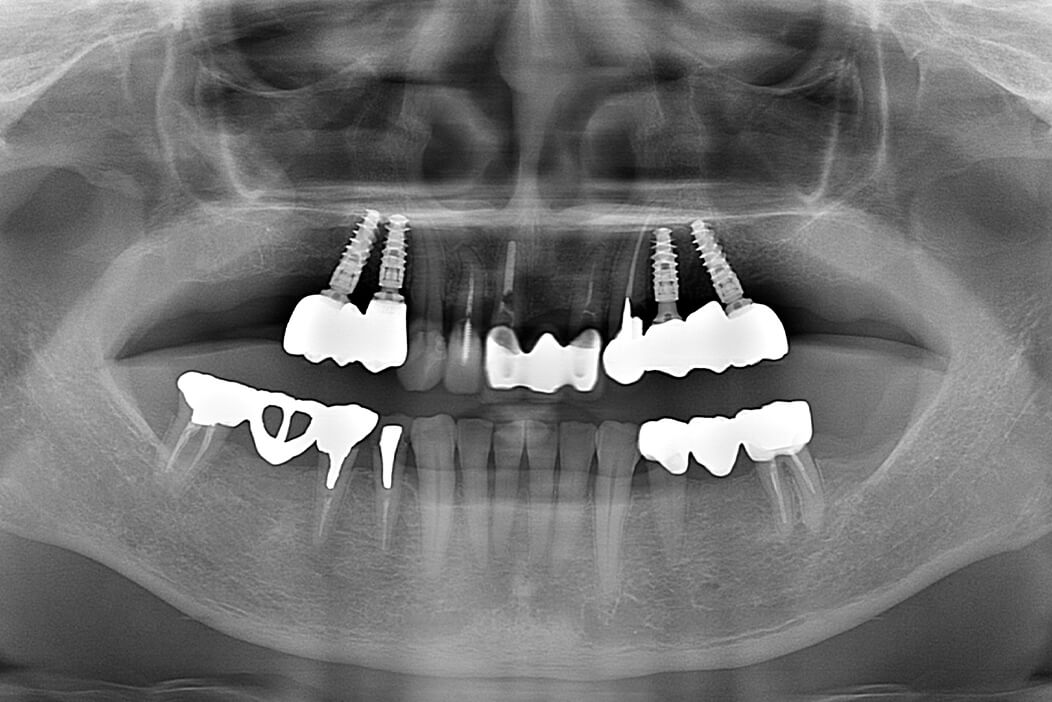

女性/60代

費用/4,527,600円(内矯正治療356,400円)

治療期間/1年5ヶ月

治療内容の詳細/

治療が苦手だが頑張って全体的に治したいと歯科治療を希望。

術前のX線、CT撮影により保存が可能な歯、不可能な歯を選別し、患者様が出来るだけ歯を残したいという希望も考慮して治療計画を立てました。

先ずは保存不可能な歯を抜歯して、臼歯部にストローマン社製ティッシュレベルインプラント、BLTインプラントを埋入し、約2ヶ月後に仮歯を入れて奥歯の噛む位置を決定し、下顎の前歯の叢生(デコボコ状態)はマウスピース矯正(クリアコレクト)を使用して歯列矯正を行い、その後上顎の前歯の欠損部にはストローマン社製BLTインプラントを埋入し、約2ヶ月後に仮歯を入れました。全体的に仮歯の状態で噛み合わせの調整をした後、口腔内スキャナーでデジタル印象を行い、自身の歯にはジルコニアセラミッククラウン、インプラント部にはスクリュー固定式のジルコニアセラミッククラウンを作成し装着しました。約1年5ヶ月の治療期間でしたが、患者様は最後まで頑張って治療を受けていただきました。